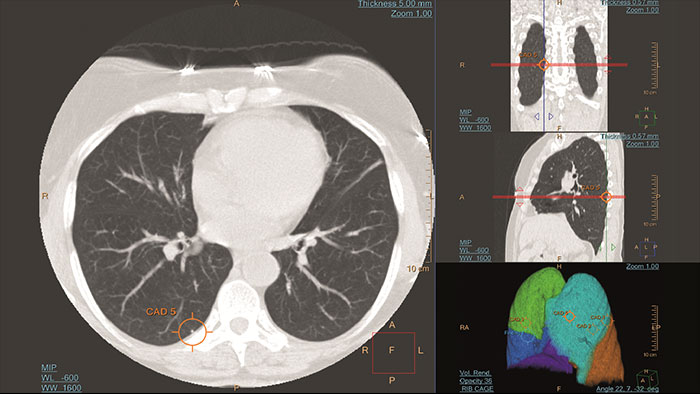

Automated computer aid for lung nodule detection

Artificial second reader to support the detection of lesions or nodules which may have been missed. It offers an automated process that identifies and marks regions of interest based on image features associated with lung nodules. It is intended for use as a second reader after an initial interpretation of the diagnostic image has been performed.

*CAD functionality not available for sale in the US.